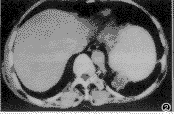

胸部CT检查: 平扫示左肺下叶后基底段主动脉旁一类圆形肿块,最大径约6.5cm,有包膜,其内低密度,均匀,CT值为15HU(图1)。增强扫描示包膜强化,但其内低密度处不强化,并见胸主动脉左后方有一分支伸向肿块(图2、3)。CT诊断为左肺下叶肺隔离症。

图1 CT平扫示左肺下叶后基底段脊柱旁胸主动脉后方一肿块,有包膜,其内为低密度,CT值为15HU

图2 CT增强扫描示左下肺后基底段肿块的下极部分,包膜强化,其内低密度不强化,并见胸主动脉有一分支伸向肿块(↑)

图3 CT增强扫描(图2的上一层面)示肿块之包膜及进入肿块的血管强化